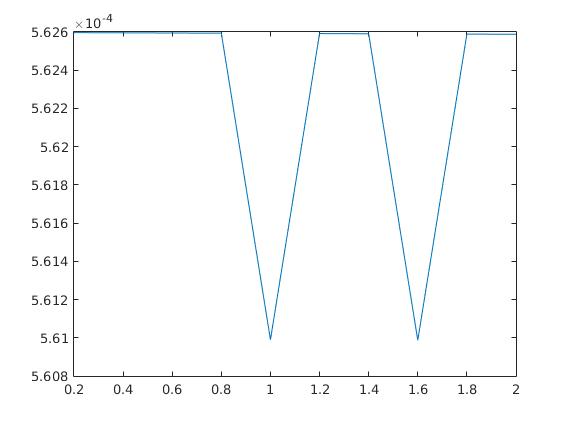

The parameters , and were optimized by comparing the final results with the existing ground truth in both cases. Here we mention that the choice of parameters is not a trivial task, since the result strongly varies with a change in the parameters. In figure 5, the scaling between the error in the -norm between exact and reconstructed image sequence per pixel per time step and the choice of each parameter out of a certain range is displayed examplarily for the heart data set. Here, we chose , and and kept two parameters fixed while plotting the error in the third one. The adaption of parameters in case of real data and, if possible, the elimination of some of them remains a future task.